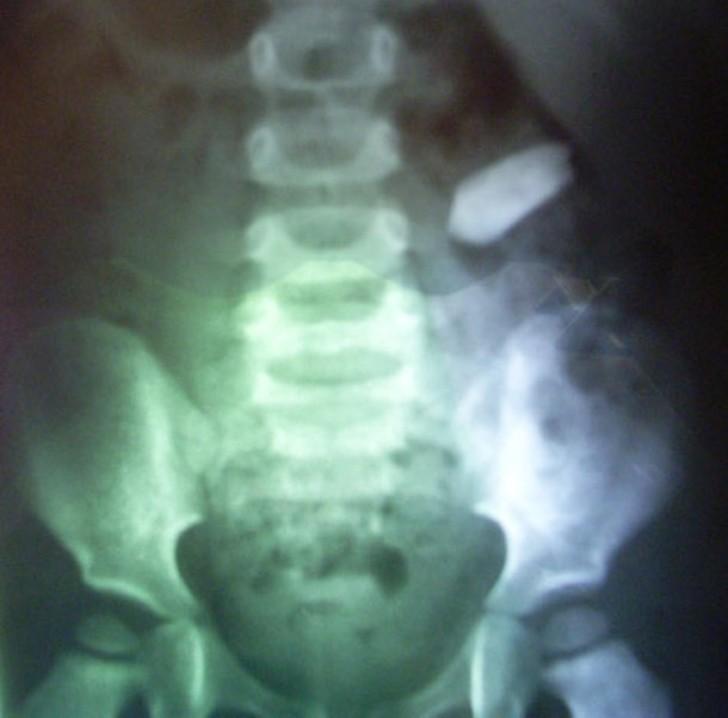

2. Пуля.